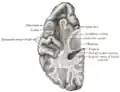

Section du cerveau montrant la surface supérieure du lobe temporal.